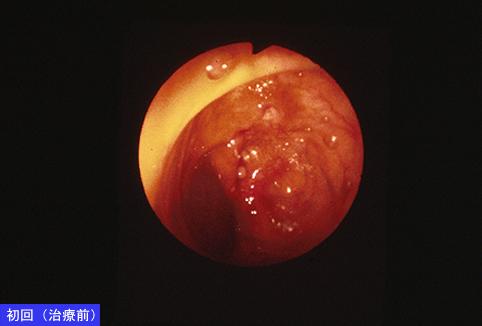

Tuberculosis de Intestino en su recuperación casi completa por la atención médica

Enfermedad Inflamatoria - Ulcerativa/Tuberculosis

colon/descendente

Endoscopia

15 - 19